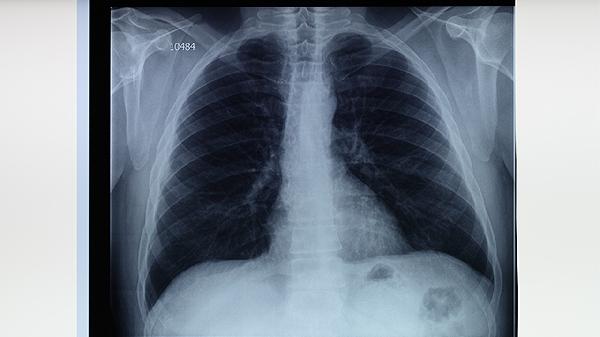

特发性肺间质纤维化

特发性肺间质纤维化是一种慢性进行性肺部疾病,主要特征为肺间质不可逆的纤维化改变,导致肺功能逐步下降。该病病因尚未完全明确,可能与遗传因素、环境暴露、免疫异常、胃食管反流、吸烟等因素有关。患者通常表现为进行性呼吸困难、干咳、乏力等症状,可通过肺功能检查、高分辨率CT等诊断。治疗方式主要包括氧疗、药物治疗、肺康复训练、对症支持、肺移植等。建议患者定期随访,积极配合医生制定个性化管理方案。